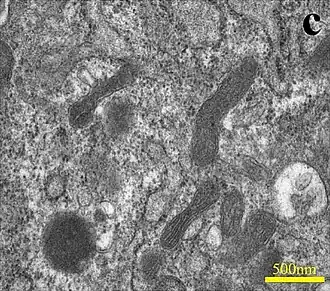

Ultraestructura

La superficie luminal de las células es normalmente de perfil liso, pero a menudo los bordes de las células vecinas pueden superponerse y entonces, puede proyectarse hacia la luz por corta distancia una cresta o lengüeta.

Las células endoteliales muestran dos tipos de uniones, las oclusivas (tigh) y otras más débiles (unión gap). Estas uniones estrechas tienen la capacidad de limitar el transporte de sustancias y moléculas, y actúan como barrera mecánica.[9]

Un rasgo llamativo de las células endoteliales es la presencia de una numerosa población de vesículas del plasmalema de unos 70 nanómetros (nm) de diámetro, de cuello delgado, que están presentes en ambas superficies celulares y que se abren a la luz y al espacio extravascular.

Los cuerpos de Weibel-Palade son estructuras de diámetro de 0,1-0,3 (μm) y una longitud de 1-5 μm.

En el corte transversal, consisten en túbulos densos a electrones con un diámetro interior de 12 nm, rodeados por una matriz menos densa y empaquetados en haces paralelos que están rodeados por una bicapa lipídica. Es donde se fabrican, almacenan y liberan dos moléculas principales, el factor de von Willebrand y la selectina P. Están ligados en la periferia de la célula a la corteza de actina y sirven como un grupo de fácil liberación.[11]